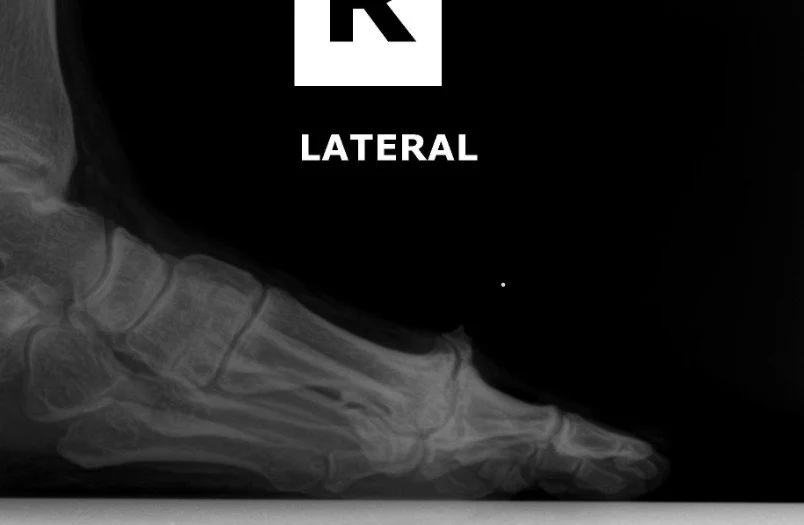

severe hallux rigidus on a lateral foot xray

• X-rays: Weightbearing AP, lateral, oblique to evaluate joint space, spurs, sesamoid changes

• A bump on top of the joint (dorsal spur)

• Limited upward motion (dorsiflexion)